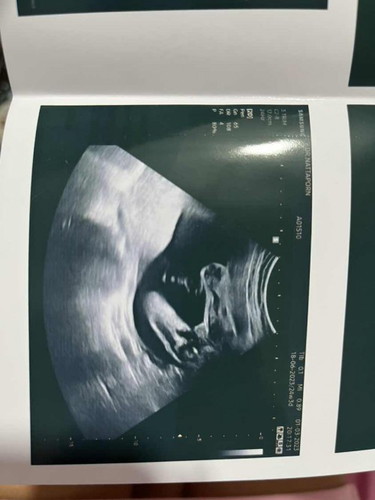

ไปซาวตอน 18w หมอบอกมีโอกาสได้ผู้หญิง 80% แล้วล่าสุดไปซาวตอน 24w1d คุณหมอบอกไม่มีอะไรออกมาจากระหว่างขา แบบนี้ได้ผู้หญิงชัวร์แล้วหรือยังคะ